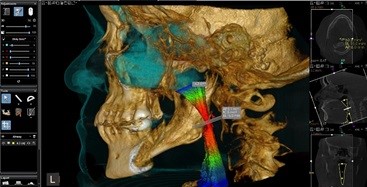

Conebeam CT scanners deliver very accurate Cranio-Maxillofacial images and combines “the power of focused-field 3D with cutting-edge panoramic imaging” for enhanced diagnostic capabilities. Our conebeam CT scanner can capture both jaws (9cm x 15cm), or one of the largest fields of vision, the complete dento-maxillofacial (18cm x 20cm) complex. This allows for a precise evaluation of the facial bones and the soft tissues associated with them. Therefore, implant placement is more precise, facial bone fractures can be diagnosed, and pathology can be evaluated.

This system allows capture of clear, detailed, anatomically correct 3D images in seconds. Comprehensive imaging software then enables rapid onscreen access of both 2D and 3D images; we can select the desired program, and the unit automatically uses the correct sensor.

The high-resolution images for each tooth let the clinician view even the smallest details from all angles and slices, while extended field-of-view capabilities enable capture of the entire mandibular or maxillary arch. This increases the level of detailed clinical information available to us, while mitigating the level of patient radiation exposure.

Our conebeam CT scan can also perform airway analysis for patients with sleep apnea, by providing a colorful three-dimensional view of your upper airway. Our airway analysis automatically segments and measures the upper airway. Automatically calculates total volume, minimal cross-sectional area, anterior/posterior and left/right measurements. Displays and updates measurement values in real time while browsing slices or changing angulations.